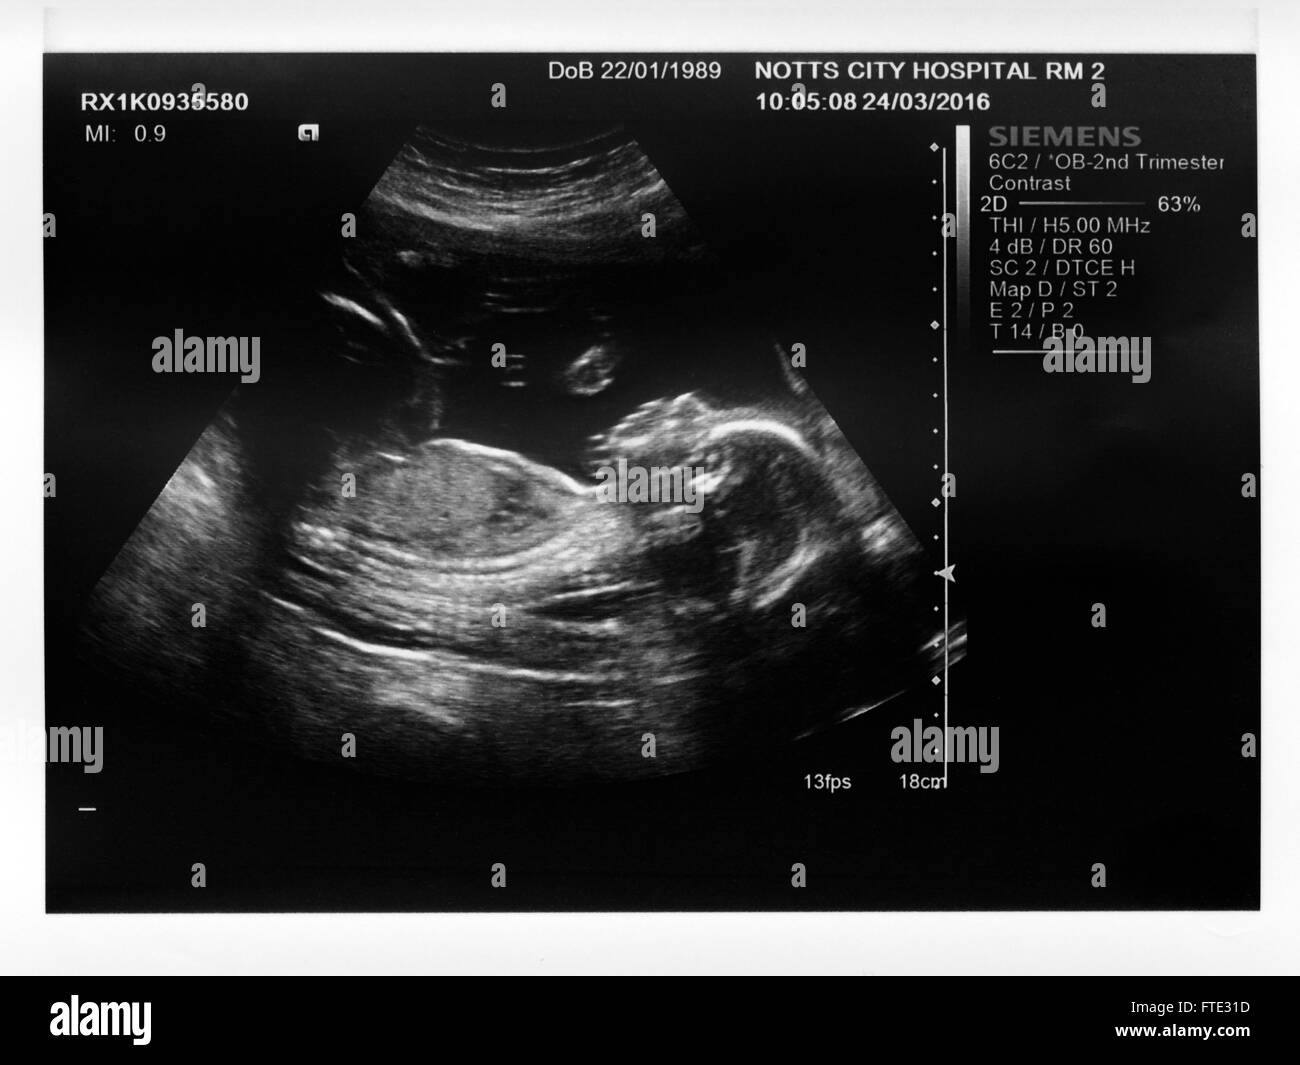

Un 2° trimestre baby boy di scansione ad ultrasuoni. (Madri nome rimosso digitalmente) Foto Stockhttps://www.alamy.it/image-license-details/?v=1https://www.alamy.it/foto-immagine-un-2-trimestre-baby-boy-di-scansione-ad-ultrasuoni-madri-nome-rimosso-digitalmente-101113305.html

Un 2° trimestre baby boy di scansione ad ultrasuoni. (Madri nome rimosso digitalmente) Foto Stockhttps://www.alamy.it/image-license-details/?v=1https://www.alamy.it/foto-immagine-un-2-trimestre-baby-boy-di-scansione-ad-ultrasuoni-madri-nome-rimosso-digitalmente-101113305.htmlRMFTE31D–Un 2° trimestre baby boy di scansione ad ultrasuoni. (Madri nome rimosso digitalmente)